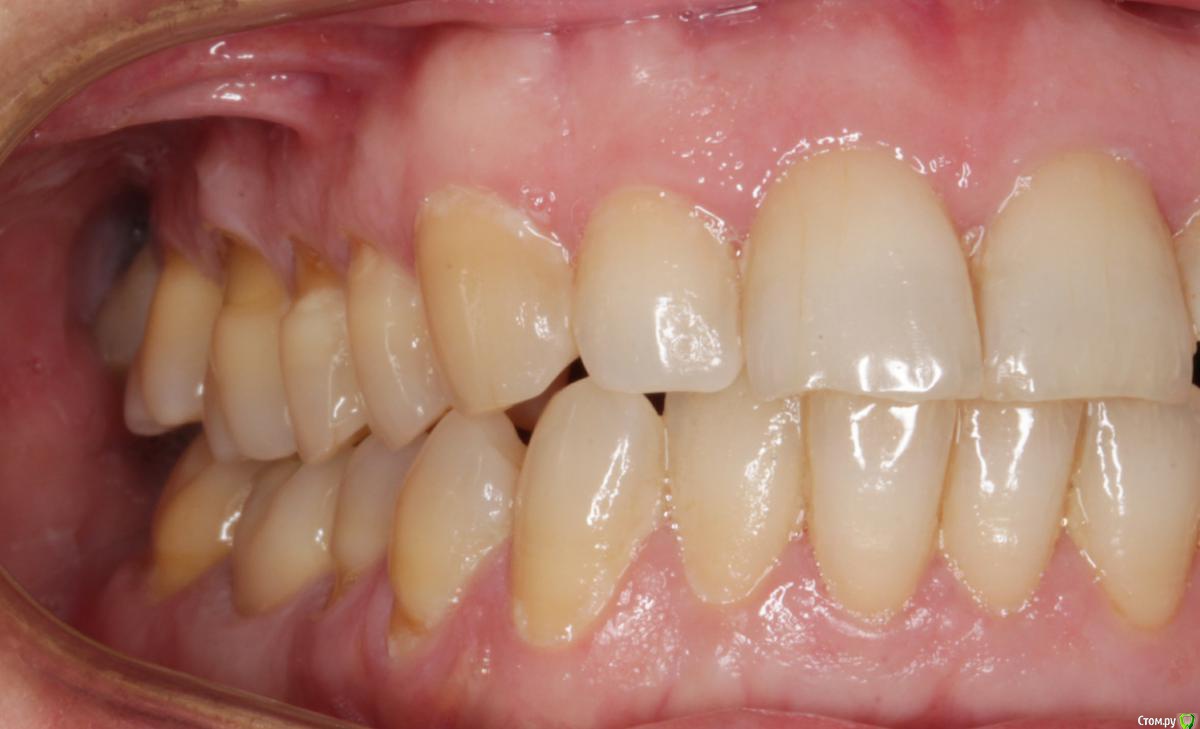

Dmitry DK Опубликовано 29 августа, 2019 Поделиться Опубликовано 29 августа, 2019 Добрый день всем! Случай достаточно заурядный, но возможно кому-то будет интересно. Результат - 2 года спустя 13 Ссылка на комментарий

Dmitry DK Опубликовано 18 сентября, 2019 Автор Поделиться Опубликовано 18 сентября, 2019 какая фиксация?Винтовая 1 Ссылка на комментарий

Дмитрий М Опубликовано 22 сентября, 2019 Поделиться Опубликовано 22 сентября, 2019 Винтоваяшахта из-за бликов не разглядел ))) Ссылка на комментарий